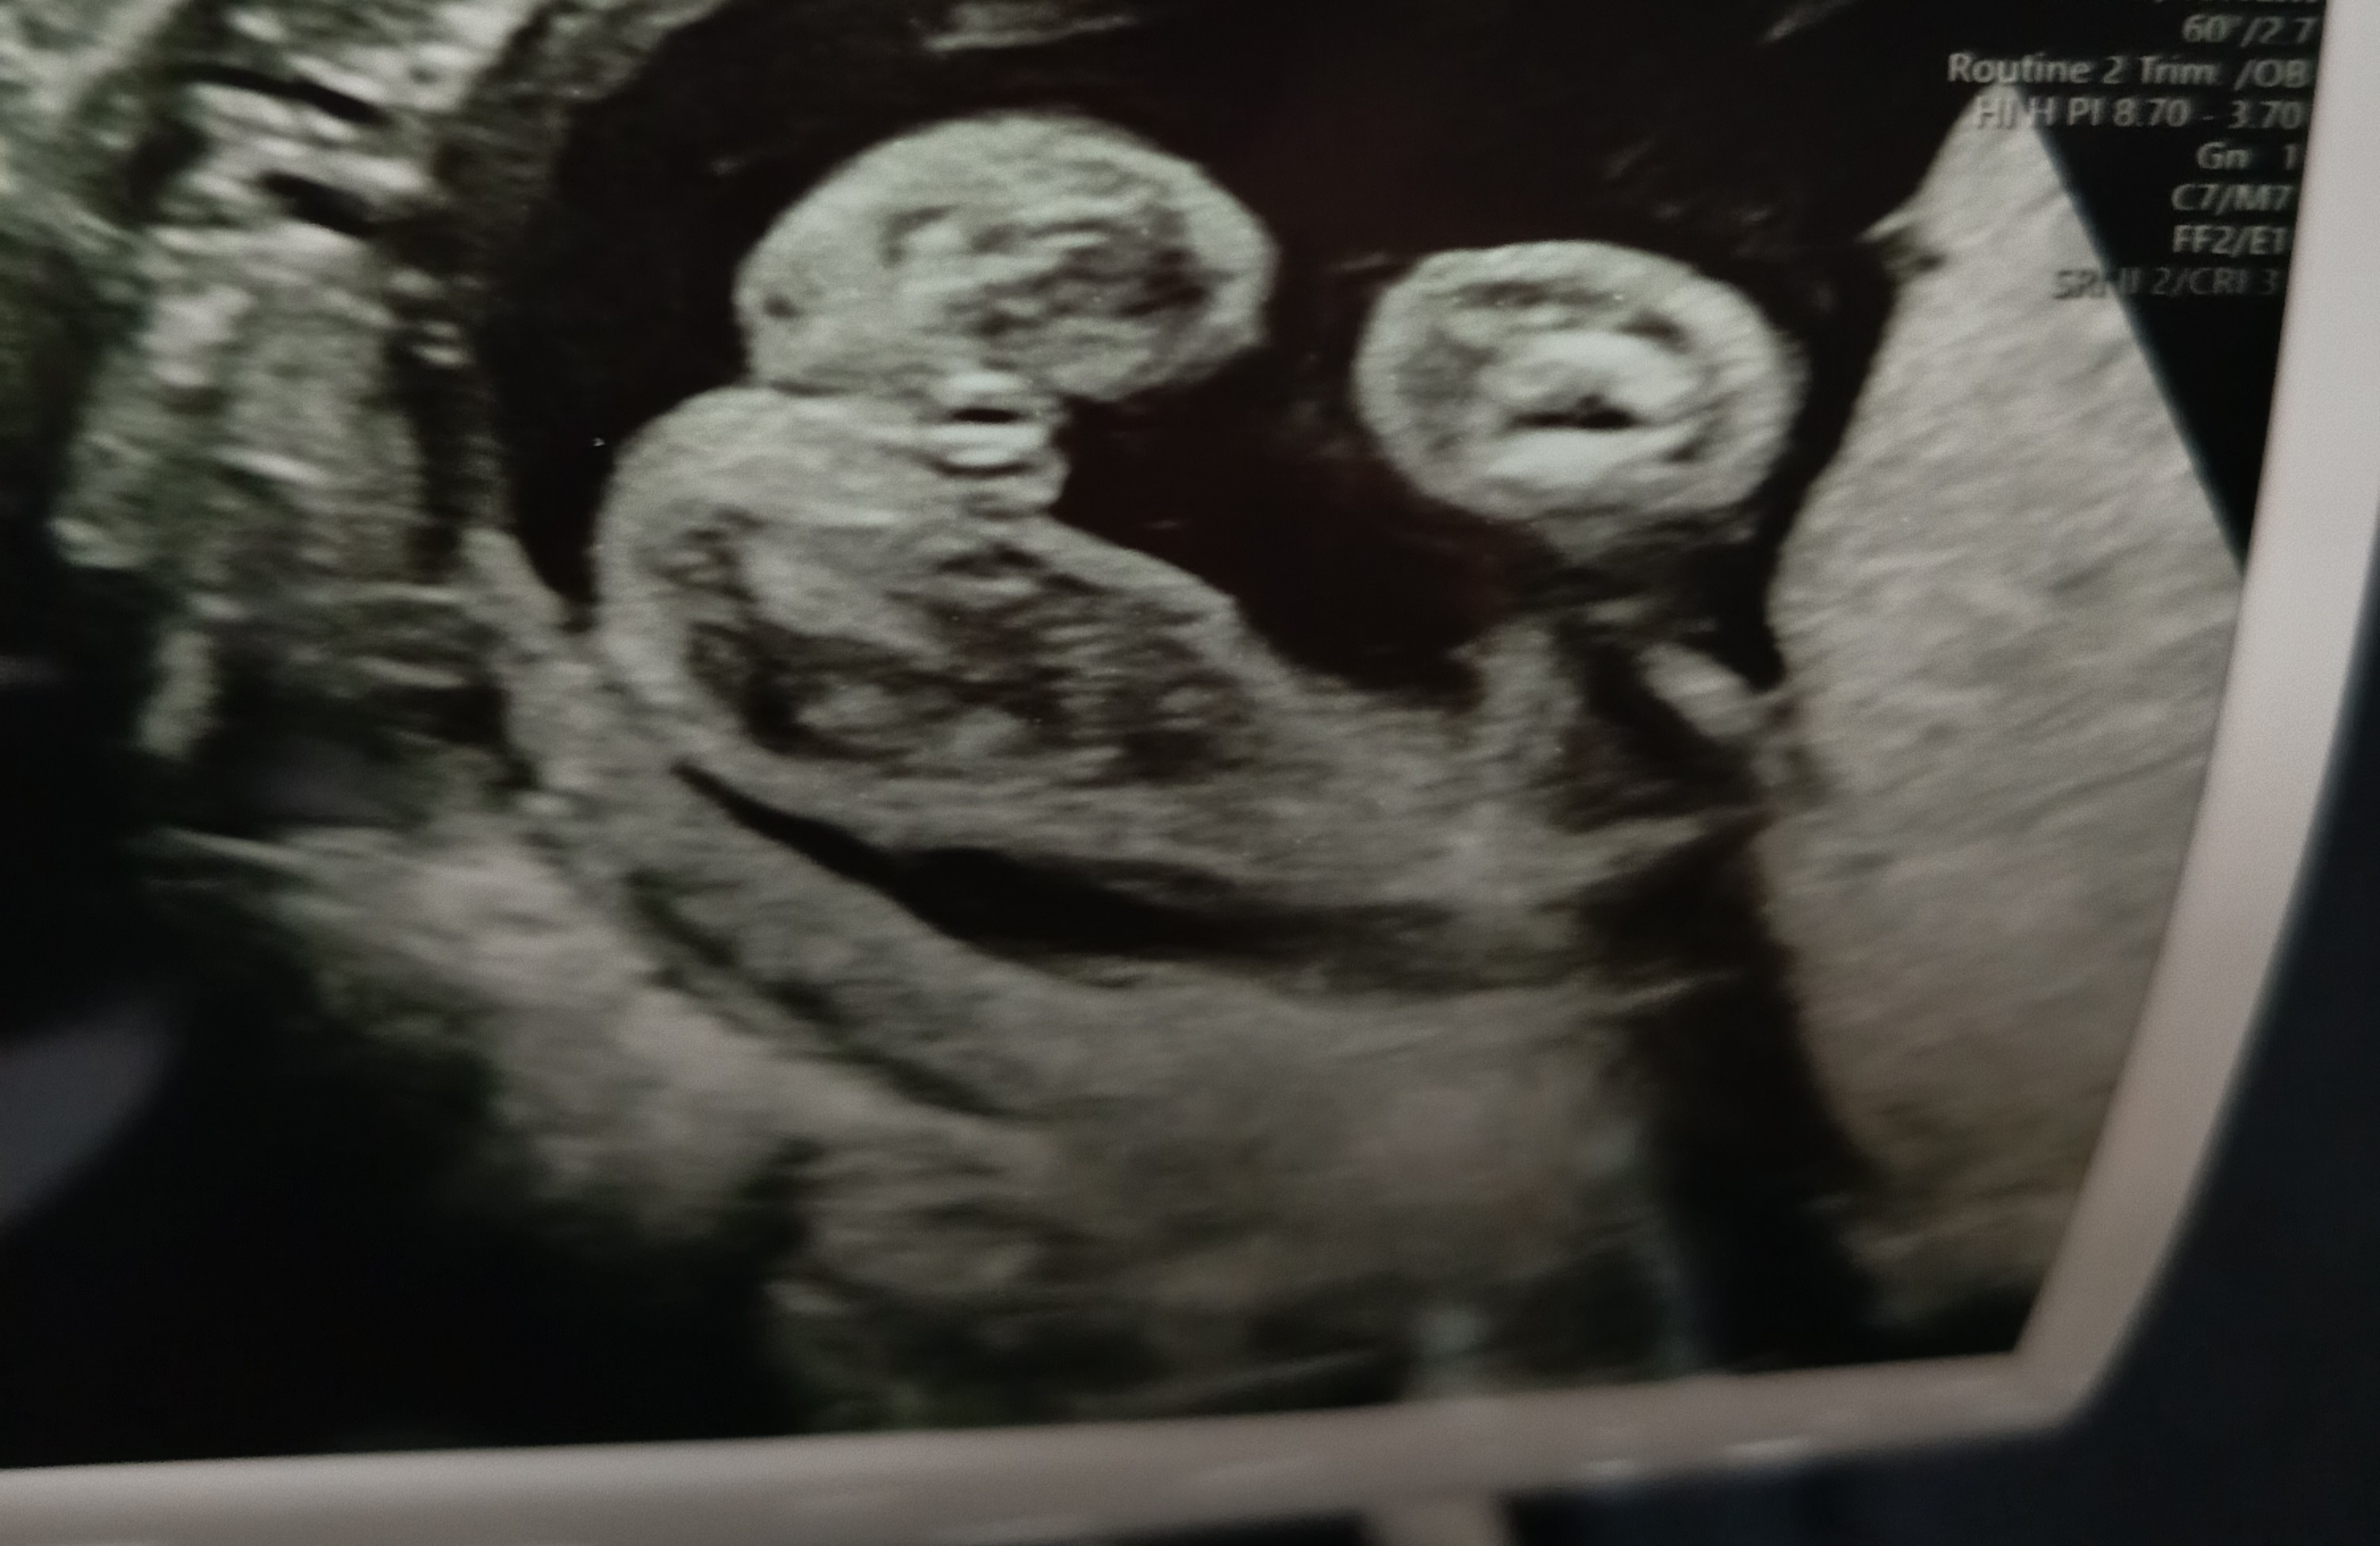

Witam jestem w 21 tygodniu ciąży byliśmy dziś na badaniu prenatalnym okazało się dziewczynka . Czy w tym tygodniu jest już wiarygodne dołączam zdjęcie USG gdzie doktor widzi że dziewczynka a my z mężem nie widzimy tam nic

• IMG_20251212_232706.jpg

IMG_20251212_232706.jpg

647,9 KB · Wyświetleń: 181